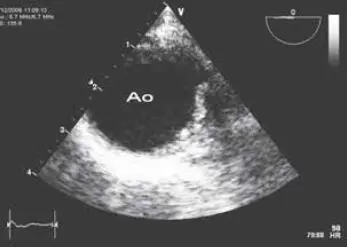

Fig 48 Proyección transversal de aorta descendente Abreviaturas Ao aorta - фото 47

Fig. 4.8 Proyección transversal de aorta descendente. Abreviaturas: Ao = aorta.